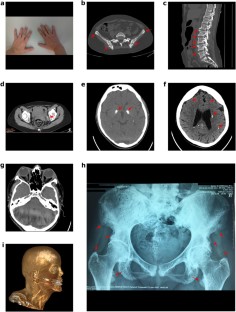

Raine syndrome is a rare hereditary disease caused by mutations in the FAM20C gene. Only 18 non-lethal cases have been reported, the majority of them being children and young adults aged up to 30. Due to the rarity of the disease, genotype–phenotype correlations are not available and patient life expectancy is unknown, thus making descriptions of each novel case of particular importance. In this article, we describe a case of an Armenian woman, living in Russia, who was followed-up from age 36 to 39, presenting with pain in the extremities, osteosclerosis with periosteal bone formation, multiple calcifications in solid organs, midface hypoplasia, exophthalmos, amelogenesis imperfecta, shortening of distal phalanges, pectus excavatum, and hypophosphatemia due to renal phosphate wasting. Whole exome sequencing was performed on NextSeq 550 (Illumina, USA) and compound heterozygous variants were identified in the FAM20C gene (reference sequence NM_020223): a frameshift insertion c.1107_1108insTACTG (p.Tyr369fs) and a missense substitution c.1375C > G (p.Arg459Gly). This is the first reported case of a middle-aged patient presenting classical symptoms of Raine syndrome caused by novel compound heterozygous mutations in the conserved C-terminal domain of FAM20C gene.